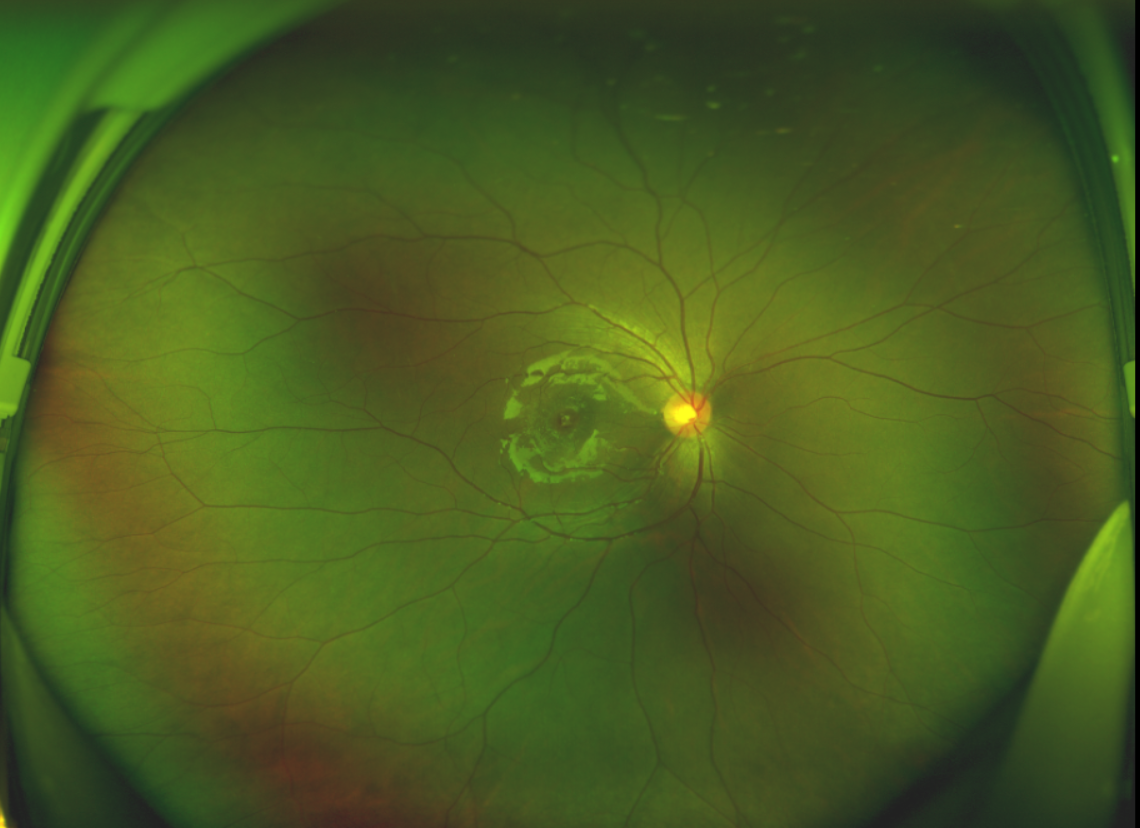

黃斑位于視網(wǎng)膜正中心,是視覺最敏銳的區(qū)域,堪稱“眼底的心臟”,負(fù)責(zé)我們閱讀、駕駛、識別人臉等精細(xì)視覺。 當(dāng)黃斑區(qū)的神經(jīng)組織出現(xiàn)全層缺損,形成一個“孔洞”,即為黃斑裂孔,它會直接導(dǎo)致中心視力急劇下降、視物變形、視野中心出現(xiàn)暗區(qū)。

由于裂孔較小,當(dāng)?shù)蒯t(yī)院建議先觀察,看看裂孔是否能夠自愈。可半年時間過去了,誠誠傷眼的裂孔不僅沒有愈合的跡象,反而越來越大,這讓家長的心揪得更緊了。

除此之外,利用自體組織覆蓋為黃斑裂孔提供了理想的愈合環(huán)境,裂孔閉合速度顯著快于傳統(tǒng)方法。誠誠接受手術(shù)24小時后,檢查可見內(nèi)界膜瓣位置良好;術(shù)后1個月,黃斑裂孔已經(jīng)閉合,視力恢復(fù)到0.5;術(shù)后兩個月,視力進(jìn)一步提升到0.7。